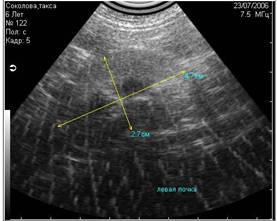

- сетевые - вызванные включёнием одновременно с УЗИ-аппаратом электрических приборов и сотовым телефоном (Рис.1; 2);

- вызванные плохим качеством выбривания кожи животного (Рис.3);

- вызванные недостаточным количеством УЗИ-геля, нанесённого на кожу (Рис.4) ;

- вызванные движениями животного, в том числе дыхательной экскурсией (Рис.5).

Рис1. Помехи, вызванные включённым рядом с аппаратом УЗИ сотовым телефоном. Во избежание этого лучше просить владельца выключать сотовый телефон при проведении ультразвукового исследования. |

Рис2. Помехи, вызванные работающими электроприборами, включёнными в сеть рядом с аппаратом УЗИ. |

Рис3. Помехи, вызванные плохим выбриванием животного (продольные полосы слева). |

Рис 4. Недостаточное количество геля при проведении УЗИ (правая половина снимка). |

Рис. 5. Помехи, вызванные дыхательными движениями животного. |